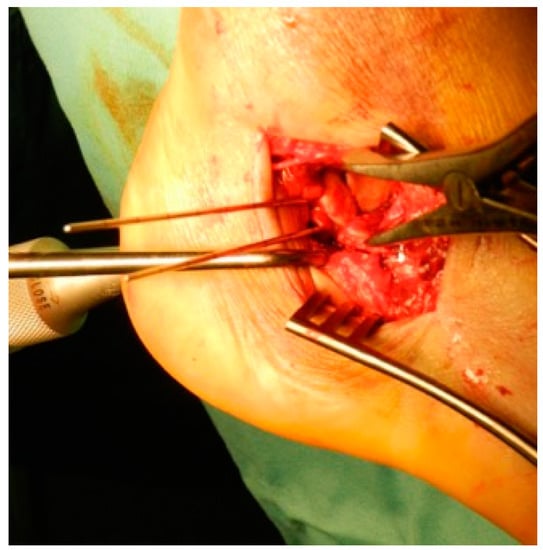

2.2. Surgical Procedure

| Fragments exposure | Release of the inferior peroneal retinaculum Release of the CFL and subtalar ligaments SJ exposure |

| Steps for fragments reduction | Reduction of the PT fragment to the sustentacular constant fragment Reduction of articular fragments from posterior to anterior |

| Osteosynthesis | Temporary fixation with K-wires IF with plate and screws |